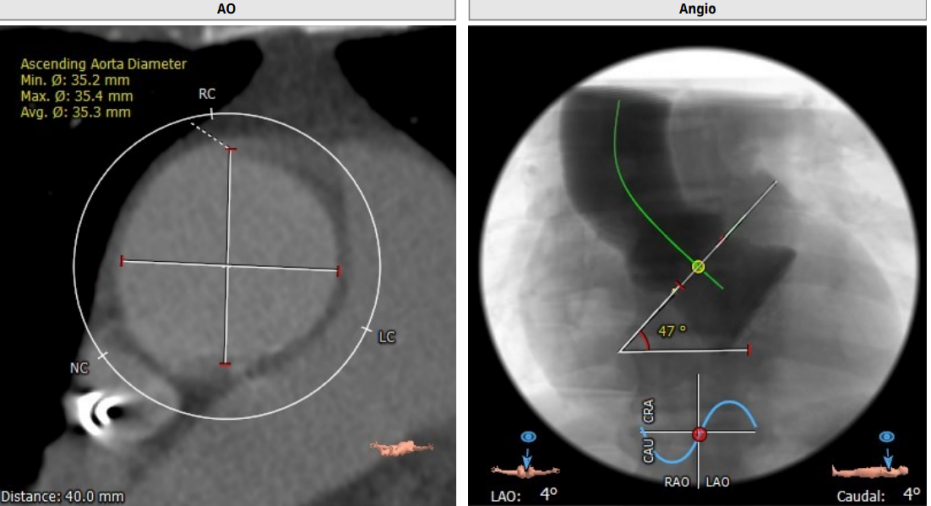

术前CT评估

瓣环:23.4mm LVOT:24.6mm

TYPE 1型二叶瓣,中重度钙化,STJ:29.3

左冠高度:10.6mm 右冠高度:17.5mm

心脏角度:47°,升主动脉40mm:35.3mm

释放体位:LAO:1°,CRA:7°左冠线切位:LAO:10°,CRA:3°

钙化积分:575mm

左室大小:43.0mm

入路情况:左股,主动脉弓部有钙化